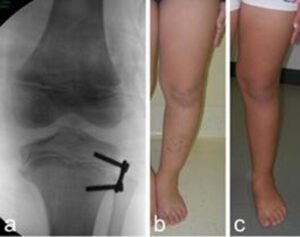

- Progressive correction with hexapodalic external fixator. This is a complex technique but it can give excellent results, especially for the most severe forms of varus knee. It allows the simultaneous correction of different aspects (varus deviation, internal rotation, shortening) limiting the vascular and neurological complications related to extemporaneous corrections. It also allows the limb to be lengthened in the same procedure.